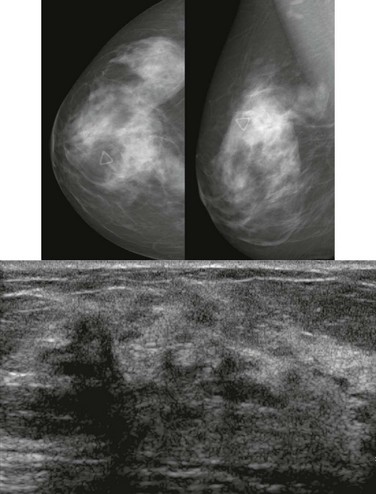

How would a web of tumor cells look on a mammogram or ultrasonography (US)? The mammogram may show only very subtle findings or be completely normal, even in the setting of extensive ILC (Fig. 11-2). Only the densest part of the tumor will be visible on mammography. ILC may appear as a mass with ill-defined or spiculated margins or as architectural distortion with or without a central mass. When a central mass is present, then it is considered a spiculated mass. When there is architectural distortion without a central mass, these lesions are often called the “dark star.” Calcifications are uncommon, though ILC can have associated DCIS. ILC is often seen in only one view, most commonly the craniocaudal (CC) view. This makes sense because the CC view has better compression of the breast tissue than does the mediolateral oblique (MLO) view. Greater compression can bring out the subtle distortion to better advantage. The extent of disease of ILC is not easily assessed on mammography because the edges of that web are not well defined.

FIGURE 11-2 ILC.

A 49-year-old woman with a firm palpable lump in the right breast. Mammogram is normal in the palpable area that is marked by a triangle. US shows multiple hypoechoic areas with shadowing but no discrete mass, which is characteristic of ILC. (Reprinted with permission from Harvey JA. Unusual breast cancers: Useful clues to expanding the differential diagnosis. Radiology 2007;242:683-694.)

On US, ILC may present as a defined mass (see Fig. 11-3) but more often presents as ill-defined areas of shadowing without a distinct mass (see Fig. 11-2). The lines and arcs of tumor can produce bands of shadowing, like the edges of a spider web. Although tumor size is often underestimated by US, this modality is more accurate than clinical examination or mammography in assessing extent of disease.